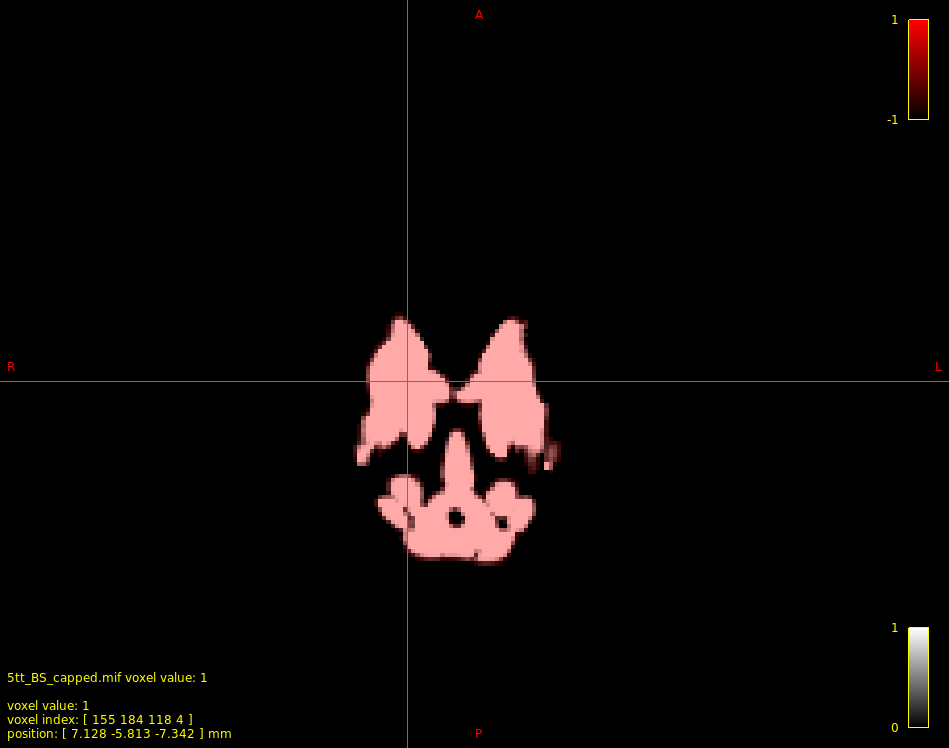

5ttedit: Support for floating-point input images #2558

That's a particularly unusual effect given that the command operates entirely independently on each voxel. @Arshiyasan any chance of sharing some data so that I can attempt to reproduce? |

Interesting... Reading the fix, I can't quite understand what the reason for those strange bands was. Did you find out what was causing that pattern? |

That was me failing to always move the thread-specific position in the input image before reading from it; therefore sometimes it would be reading input image data from a previously-processed voxel. |

@Arshiyasan Feel free to give a try if you'd like; might be preferable to thresholding at 0.5.

(currently a zero in an input image means don't make any modification)